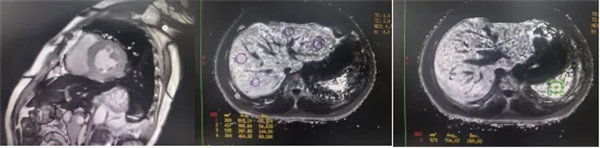

CMR是目前唯一能定量检测组织铁负荷的无创影像学手段,主要依赖其 T2*mapping技术测量的T2*弛豫时间(T2*值)间接量化组织铁含量。当CMR检测出心肌T2*<20 ms时,初步诊断心肌铁过载,T2*值<10-15ms时,提示心功能受损风险显著增加。T2值越低,铁沉积越严重。目前T2*mapping技术检测T2*已作为临床诊断肝脏、心肌铁过载的首选无创检查,也被用作随访工具评估疾病进展和疗效。

肝脏和脾脏信号改变 矢状位梯度回波定位图像可显示肝脏和脾脏信号降低,提示肝脾铁沉积,T2*>6.3及R2*>160/s表现中度铁过载。